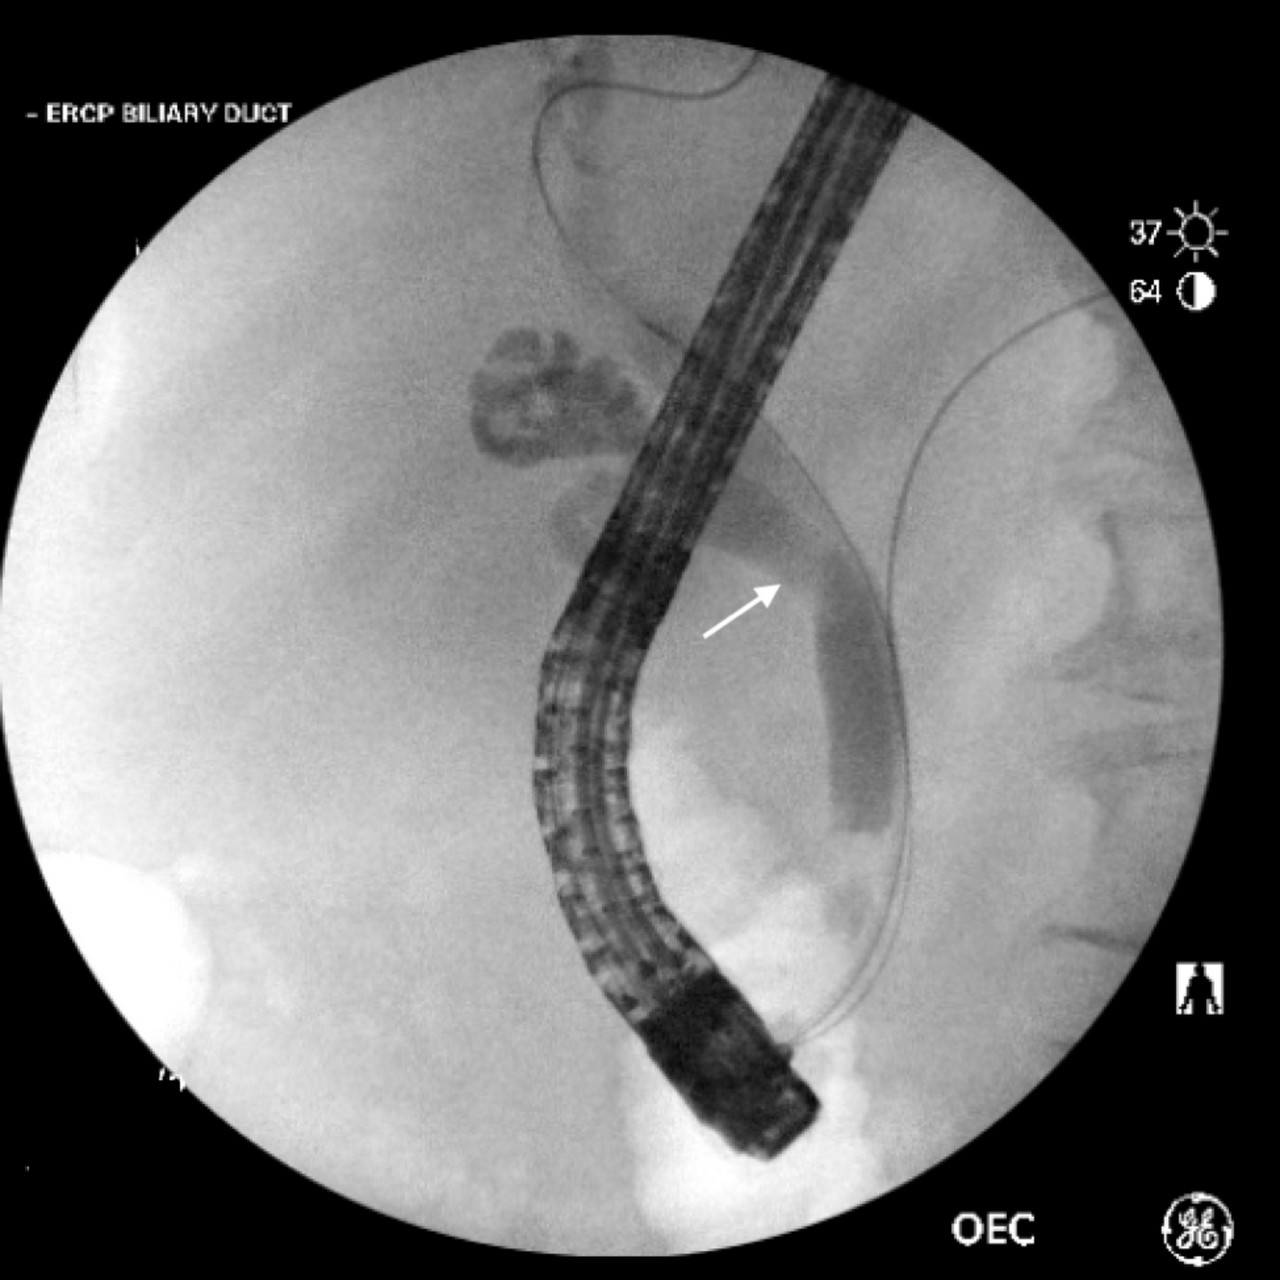

3. 내시경적 역행성 담췌관 조영술(ERCP) 내시경적 역행성 담췌관 조영술은 담관을 통해 담석의 위치를 조사하여 이를 제거하기 위한 진단 및 치료를 위하여 사용됩니다. 시행 방법은 약하게 마취를 하고 내시경을 목구멍을 통과하여 위를 거쳐 십이지장까지 넣습니다. 의사는 내시경을 조정하여 담관 안에 카테터를 넣고 조영제를 주사하여 이미지를 찍습니다. 이 방법은 문제가 있는 담관과 담석의 위치를 볼 수 있으며 확인된 담석은 내시경에 장착된 기구를 이용하여 제거할 수 있습니다.

2. 내시경적 치료 만약 담석이 담관내에 존재한다면 담낭 수술 전 또는 담낭 수술 중 역행성 담췌관 조영술을 이용하여 담석의 위치를 알아내고 동시에 내시경을 통하여 담석을 제거할 수도 있습니다. 과거에 담낭절제술을 받은 사람이 수술 후 몇 주, 몇 개월 또는 몇 년 후에 담관내의 담석을 진단받기도 하였는데, 이러한 경우 내시경적 역행성 담췌관조영술 및 내시경적 담석제거술을 통하여 담석을 무사히 제거할 수 있습니다.